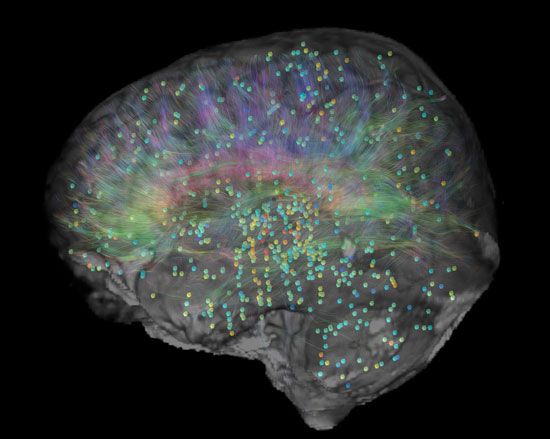

Σύμφωνα με τον διευθύνοντα σύμβουλο του Ινστιτούτου Αλαν Τζόουνς οι πληροφορίες για τη δημιουργία του χάρτη προήλθαν από την ανάλυση δύο ανθρώπινων εγκεφάλων η λειτουργία των οποίων κατεγράφη με μαγνητική τομογραφία (MRI) καθώς και με μια παραλλαγή της συμβατικής μαγνητικής τομογραφίας η οποία ονομάζεται απεικόνιση τανυστή διάχυσης (Diffusion Tensor Imaging, DTI).

Ολες αυτές οι πληροφορίες συνέθεσαν τελικώς τον λεπτομερή χάρτη στον οποίον ο χρήστης μπορεί να αναζητήσει 1.000 ανατομικές περιοχές καθώς και περισσότερα από 100 εκατομμύρια σημεία που μαρτυρούν τη γονιδιακή έκφραση αλλά και τη βιοχημεία καθεμιάς από τις 1.000 αυτές περιοχές.

Για παράδειγμα ένας ερευνητής θα μπορούσε να δημιουργήσει πολύ γρήγορα μια τρισδιάστατη απεικόνιση των σημείων του εγκεφάλου στα οποία εκφράζονται οι βιοχημικοί στόχοι ενός αντικαταθλιπτικού φαρμάκου. Γενικότερα, ο νέος ολοκληρωμένος ηλεκτρονικός χάρτης αναμένεται να αποδειχθεί πολύτιμος για τους επιστήμονες που μελετούν τα «μυστικά» του εγκεφάλου και προσπαθούν να αναπτύξουν αποτελεσματικούς τρόπους αντιμετώπισης των παθήσεών του.